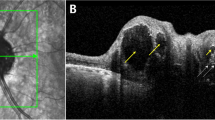

Twenty-three patients with BD and 23 controls underwent retinal evaluation using SS deep range imaging (DRI) Triton OCT. Full retinal thickness, the ganglion cell layer (GCL), the retinal nerve fiber layer (RNFL), and choroidal thickness were evaluated with automated segmentation software.

Patients with BD were shown to have significant thinning of the macular full retinal thickness in the center (p = 0.049), inner temporal (p = 0.045), inner nasal (p = 0.016), and inner inferior (p = 0.016) of the ETDRS areas. The macular GCL layer was reduced in patients compared with controls (average, p = 0.002; superior, p = 0.009; superonasal, p = 0.009; inferonasal, p = 0.003; and inferior, p = 0.009). Peripapillary reduction of full retinal thickness (average, p < 0.001; superotemporal, p < 0.001; superonasal, p = 0.003; nasal, p = 0.005; and inferotemporal, p = 0.033), GCL (nasal, p = 0.025), and RNFL thickness (average, p = 0.002; superotemporal, p < 0.001; and superonasal, p = 0.045) was observed in patients compared with controls. No significant differences were observed in choroidal thickness measurements.

BD patients were shown to have quantifiable thinning of full retinal thickness and the GCL in the macular area, as well as a peripapillary reduction of the RNFL and GCL thickness. The analysis of the retinal sublayers with SS-OCT may be a useful indicator to show degeneration and monitor disease progression in bipolar disorder.